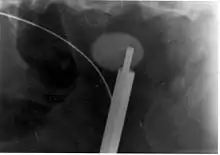

Ureteroscopic surgery

Ureteroscopy has become increasingly popular as flexible and rigid fiberoptic ureteroscopes have become smaller. One ureteroscopic technique involves the placement of a ureteral stent (a small tube extending from the bladder, up the ureter and into the kidney) to provide immediate relief of an obstructed kidney. Stent placement can be useful for saving a kidney at risk for postrenal acute kidney failure due to the increased hydrostatic pressure, swelling and infection (pyelonephritis and pyonephrosis) caused by an obstructing stone. Ureteral stents vary in length from 24 to 30 cm (9.4 to 11.8 in) and most have a shape commonly referred to as a "double-J" or "double pigtail", because of the curl at both ends. They are designed to allow urine to flow past an obstruction in the ureter. They may be retained in the ureter for days to weeks as infections resolve and as stones are dissolved or fragmented by ESWL or by some other treatment. The stents dilate the ureters, which can facilitate instrumentation, and they also provide a clear landmark to aid in the visualization of the ureters and any associated stones on radiographic examinations. The presence of indwelling ureteral stents may cause minimal to moderate discomfort, frequency or urgency incontinence, and infection, which in general resolves on removal. Most ureteral stents can be removed cystoscopically during an office visit under topical anesthesia after resolution of urolithiasis.[101]